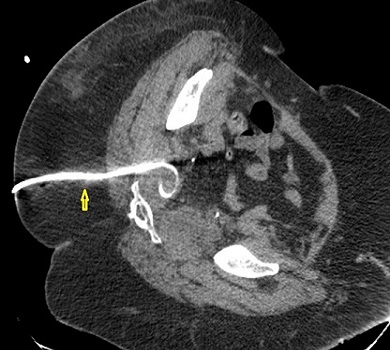

Παρακάτω φαίνονται οι παροχετεύσεις (κίτρινα βέλη) που καταλήγουν εντός των αποστηματικών κοιλοτήτων σε διάφορες τομές της αξονικής τομογραφίας.